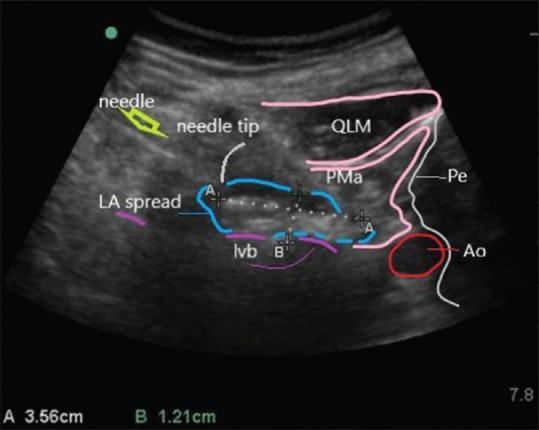

The outcomes of plexus and peripheral nerve blocks depend on needle-nerve contact and the spread of local anesthetic (LA) around the plexus or nerve. Needle-nerve distance and spread of LA could be visualized during US-guided lumbar plexus block (LPB).

After Institutional Ethics Committee approval and after obtaining informed consent, 24 American Society of Anesthesiologists'-physical status I-III patients who underwent surgical fixation of fractures of proximal femur were enrolled. Spinal anesthesia was a primary anesthetic in all patients. At the end of the surgery, all patients received US and neurostimulation-aided LPB at the third lumbar nerve root (LNr). The primary aim was to determine the spread of LA in the lumbar plexus area with the relation of the needle tip and LNr contact. The secondary aim was to understand block efficacy in terms of pain scores monitored at regular intervals and 100 mg intravenous tramadol was administered as a rescue analgesic if VAS >4.

In all 24 patients, we observed an oval and antegrade LA spread after lumbar plexus was identified with neurostimulation at L3. With the needle closer to intervertebral foramina (IVF), a retrograde spread was visualized. Only 2/24 patients received rescue analgesia in the first 24 h.

在所有24例患者中,在L3处通过神经刺激确定腰丛后,我们观察到LA呈椭圆形且向前扩散。当针靠近椎间孔(IVF)时,可观察到逆行扩散。仅2/24例患者在最初24小时内接受了补救镇痛。

The type of spread after the US-guided LPB could predict block success of block and a possible epidural spread.

超声引导下腰丛阻滞后的扩散类型可预测阻滞的成功与否以及可能的硬膜外扩散。